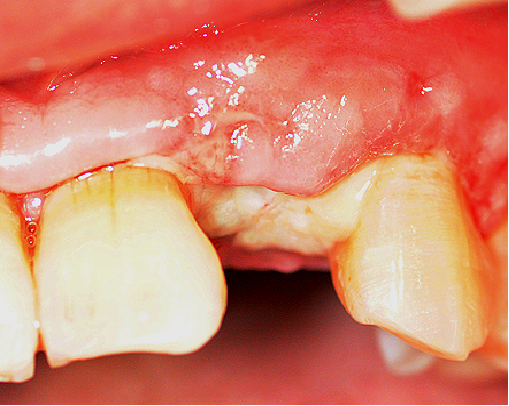

采用不切开骨膜的软组织扩张术——Soft Tissue Extend释放软组织张力

记录翻瓣后原始软组织瓣长度,使用软组织搔刮器(Soft Tissue Extender)冠根向搔刮软组织瓣。

在不切断骨膜的前提下,使用软组织刮治器反复搔刮软组织瓣,可以起到延长软组织瓣的作用。

使用软组织搔刮扩张前后对比:可见在不切断骨膜的前提下,使用软组织搔刮即可获得软组织瓣延长8-9mm。

软组织减张创口管理关闭至关重要。由于拔牙创口的存在,常存在软组织不足创口关闭困难的问题,同时引导骨再生术中一般需要过量植骨,软组织瓣张力释放十分重要。本病例没有沿用经典的骨膜切开减张方法,而是遵循保留“血供最大化”的理念,尝试自创的不切开骨膜的软组织瓣搔刮扩张技术——Soft Tissue Extend,获得了延长软组织瓣8-9mm,实现了软组织瓣的有效减张,也保存了骨膜及骨膜上软组织微血管网的完整性、进而最大限度保留了骨再生区的血供,减少创缘血供不良导致裂开、感染的风险。